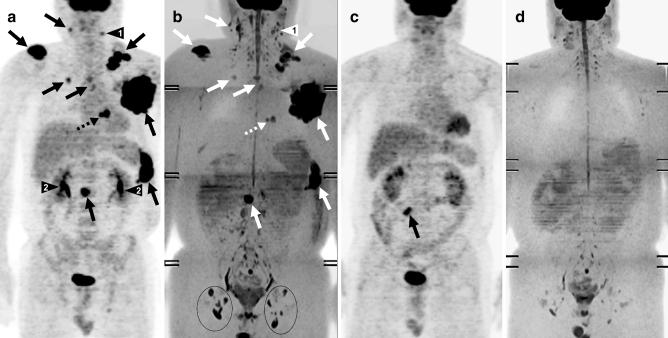

背景体部信号抑制的扩散加权全身成像(DWIBS):肿瘤学中的特征及潜在应用

Diffusion-weighted whole-body imaging with background body signal suppression (DWIBS): features and potential applications in oncology.

Diffusion-weighted magnetic resonance imaging (DWI) provides functional information and can be used for the detection and characterization of pathologic processes, including malignant tumors. The recently introduced concept of "diffusion-weighted whole-body imaging with background body signal suppression" (DWIBS) now allows acquisition of volumetric diffusion-weighted images of the entire body. This new concept has unique features different from conventional DWI and may play an important role in whole-body oncological imaging. This review describes and illustrates the basics of DWI, the features of DWIBS, and its potential applications in oncology.

摘要